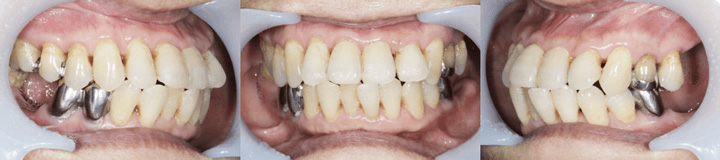

下の患者様をご覧ください。上下ともに奥歯が抜けていますが、前歯は上下ともに残っています。

このような患者様に対する入れ歯治療はポイントさえ押さえれば、それほど難しくありません。